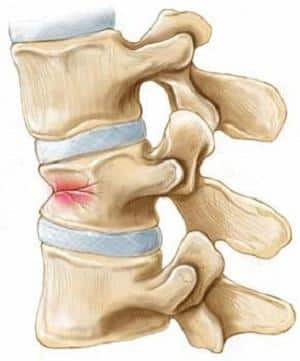

По степени различают 1, 2 и 3 степени, в зависимости от нанесенного ущерба и сокращения высоты позвонка. Сокращение высоты происходит как минимум на треть, а при более сложных травмах – на половину и более.

Последствия компрессионного перелома грудного отдела позвоночника наиболее опасны.

Сжатие нервных окончаний в теле позвонков th1-th12 вызывает патологии легких, сердца, пищеварительного тракта, а также неврологические нарушения.